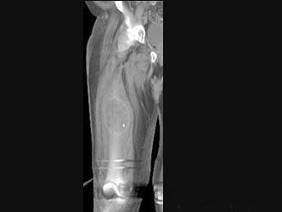

问题 男,18岁,右股骨肿瘤术后,现大腿中部疼痛、肿胀,夜间尤甚,结合CT图像,最可能的诊断是 ( )

选项 A、成骨性骨转移瘤 B、化脓性骨髓炎 C、Ewing肉瘤 D、骨肉瘤 E、骨纤维肉瘤

答案 D